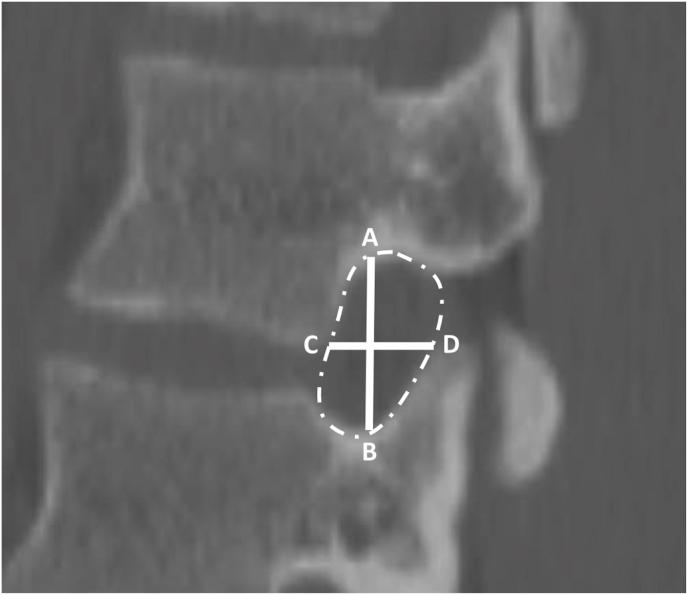

We analyzed CT imaging of 350 female and 350 male patients. Anterior, middle, and posterior DSH were measured. NFD were defined as sagittal anterior-to-posterior (AP) width, axial AP width, foraminal height, and area. Statistical analyses were performed to assess associations among DSH, NFD, and patient height, weight, body mass index, sex, and ethnicity.

材料与方法

我们分析了350名女性和350名男性患者的CT影像。测量了椎间盘间隙的前、中、后高度。NFD定义为矢状面的前后(AP)宽度、轴向AP宽度、椎间孔高度和面积。进行了统计分析以评估DSH、NFD与患者身高、体重、体重指数、性别和种族之间的关联。